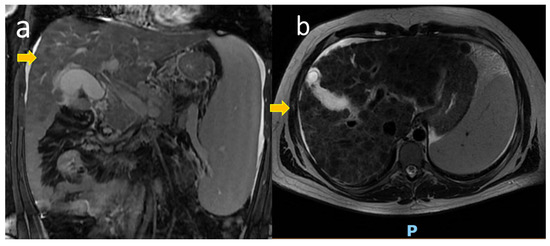

| Abdominal US | Normal liver volume with irregular and cocooned margins and a non-homogeneous echostructure. Hypoechoic nodular formation in the 7th segment of 15 mm. Splenomegaly | Mild hepatic steatosis |